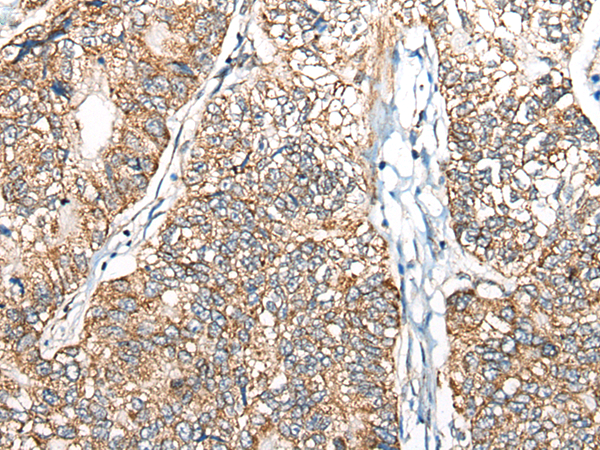

分类: 科研抗体货号: P09389别名:应用: WB,IHC反应种属: Human